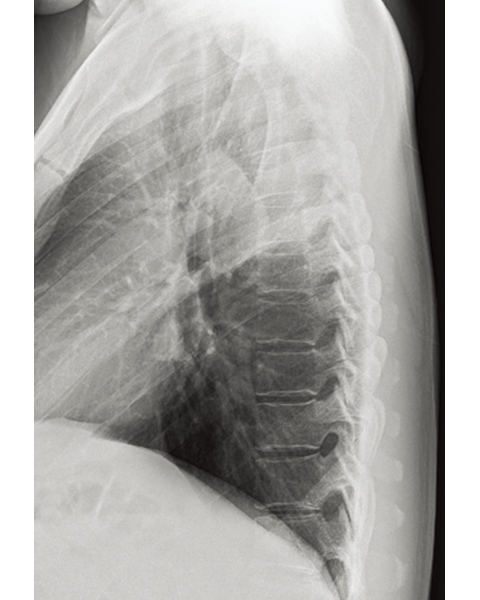

Multiple body parts supported

Abdomen

Cervical Spine

Thoracic Spine

Lumber Spine